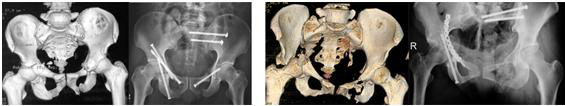

图为:骨盆髋臼骨折经皮微创固定

FIGURE: Percutaneous fixation of pelvic ring and acetabulum fractures.